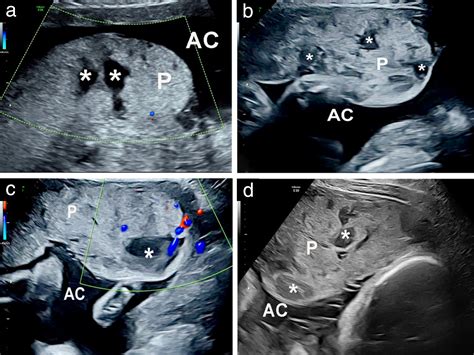

The placenta is a temporary organ that develops in the uterus during pregnancy. It serves as a lifeline between the mother and the fetus, facilitating the exchange of nutrients, gases, and waste products. Lakes In The Placenta refer to small, fluid-filled spaces within the placental tissue. These lakes are not typically visible to the naked eye but can be detected through advanced imaging techniques and histological examinations.

• Ultrasound Imaging: High-resolution ultrasound can sometimes detect the presence of lakes, although this method is not always reliable.

• Magnetic Resonance Imaging (MRI): MRI provides detailed images of the placenta and can help identify lakes more accurately.

• Histological Examination: Post-delivery, a histopathological examination of the placenta can confirm the presence of lakes.

While these methods are effective, they are not routinely used in all pregnancies. Lakes In The Placenta are often discovered incidentally during routine prenatal check-ups or post-delivery examinations.

• placental lake on ultrasound

• placental lake vs cyst